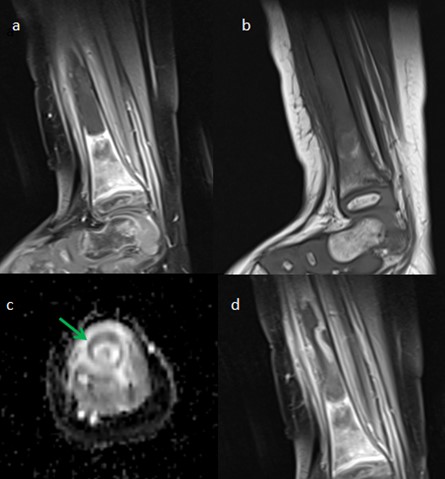

1. Sagital DP con saturación grasa, donde se identifica una expansión de la médula ósea con señal muy heterogénea del tercio distal de la tibia con áreas hiperintensas compatibles con edema óseo y área hipointensa central asociada a despegamiento perióstico compatible con reacción perióstica circunferencial.

2. Sagital T1 sin contraste con importante hipointensidad de la señal medular del tercio distal de la tibia.

3. ADC donde se observa restricción de la difusión muy llamativa en el área de la reacción perióstica (flecha verde).

4. Sagital T1 con contraste intravenoso y saturación grasa, donde se observa una captación muy heterogénea con áreas de hipocaptación central e hipercaptación periférica con importante reacción perióstica asociada. También se identifica edema e hipercaptación de las partes blandas adyacentes.